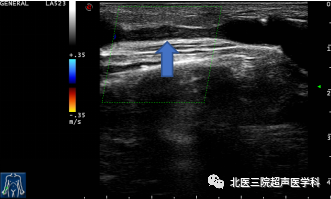

瘘口周围血肿